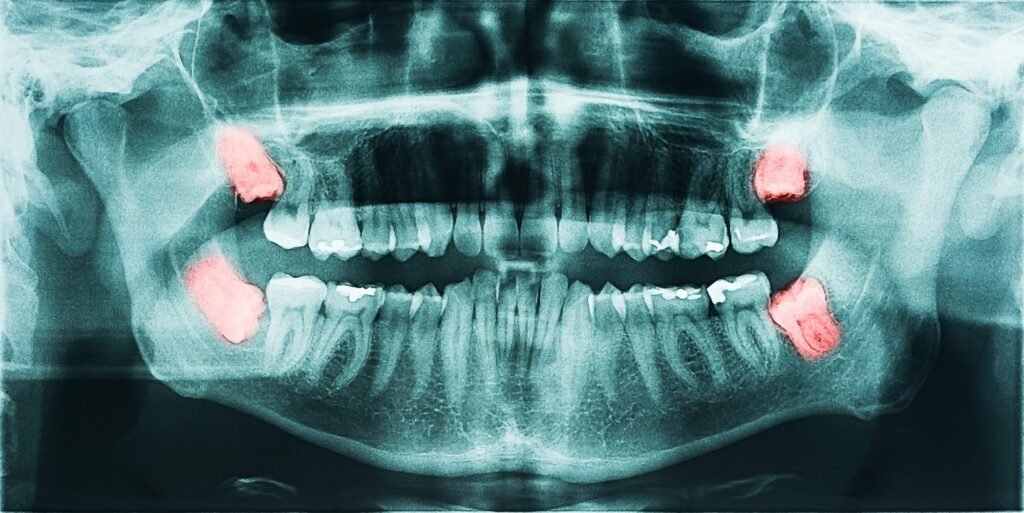

3-Yirmi Yaş Dişleri

İnsan türü Afrika’dan göç ettikçe çeşitli yaşam alanlarına yerleşti ve nihayetinde insan medeniyetleri gelişti. Bu olaylarla aynı zamana denk gelen bir şekilde, insan beslenmesinde yumuşak ve işlenmiş gıdaların tüketimine doğru bir kayma yaşandı ve bu da büyük ve güçlü çenelere olan ihtiyacı giderek ortadan kaldırdı.

Çenenin küçülmesiyle birlikte, azı dişleri, özellikle de üçüncü azı dişleri veya yirmi yaş dişleri, gömülü kalmaya oldukça yatkın hale geldi. Yirmi yaş dişleri giderek daha fazla doğuştan eksik hale geliyor. Sonuç olarak, artık insan vücudunun bir kalıntı özelliği olarak kabul ediliyorlar.